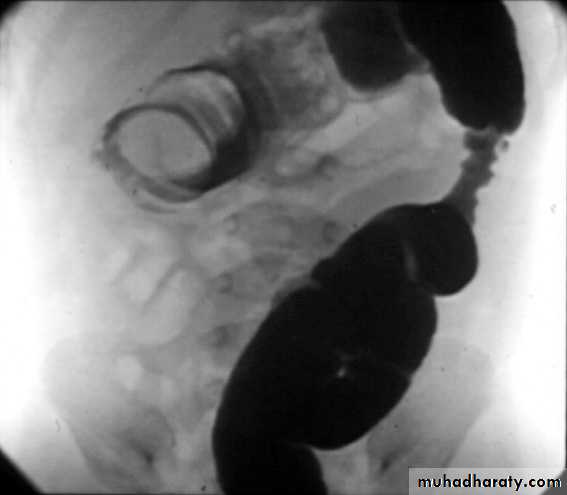

P/R:Dx.1. Plain radiograph

2. US

3. Contrast enema